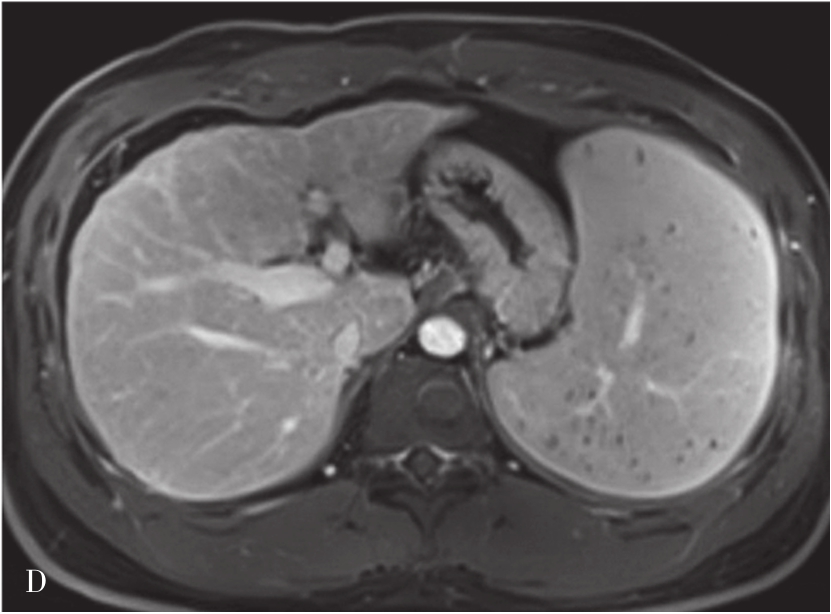

图5-21-42 HCC患者的MRI图像

A.T 2 WI脂肪抑制图像,可见肝右前叶内较大略高信号为主的病灶,内有点状更高信号影及中央低信号区,边界较清楚;B.600s/mm 2 时DWI图像,可见病灶为略高信号为主,中央略低信号;C.脂肪抑制图像,可见病灶为低信号影,边界较清楚,其内有一高信号影(箭头),为出血信号;D.增强扫描动脉期图像,可见病灶内轻微强化;E.可见门脉期图像病灶不均匀强化;F.可见延迟期图像病灶大部强化,中央无强化,假包膜清楚

HCC最常见的MRI表现为T 1 WI呈略低信号,T 2 WI呈略高信号,DWI呈高信号(图5-21-42)。有文献报道T 1 WI呈等信号者,多为分化较好的早期HCC,而脂肪变、出血、坏死、细胞内糖原沉积或铜沉积可导致病灶在T 1 WI上呈高信号,此外,在肝血色病基础上发生的HCC,由于肝实质在各脉冲序列图像上信号均很低,病灶一般都呈相对高信号。肿瘤假包膜可见于40%~70%的结节型和巨块型HCC。Gd-DTPA增强较为特征性的强化形式是对比剂“快进快出”,其原理为这些病灶70%的血供来自肝动脉,延迟相上出现宽0.5~3mm的包膜强化也颇具特征。采用特异性肝细胞摄取的对比剂,比如钆塞酸二钠(Gd-EOB-DTPA,普美显)不仅有其他钆类对比剂同样的动态增强外,在静脉注射10~30min内约有50%被正常肝细胞摄取,而不含正常肝细胞的HCC则很少或基本不摄取,而在肝特异性期呈低信号。有助于小HCC与肝硬化再生结节和其他良性病变的鉴别。大多数HCC在肝特异性期呈现相对低信号,但约10%的分化程度较好的HCC亦可呈等或高信号。